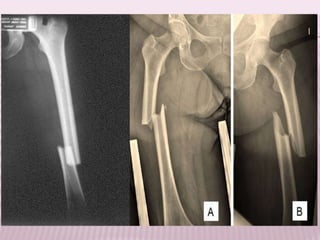

TRATAMIENTO DE LAS FRACTURAS EXTRACAPSULARES

Tratamiento conservador Pacientes con patologías graves

Debe iniciarse con el

movilización para evitar

complicaciones del

encamamiento.

OSTEOSINTESIS con tornillo placa

deslizante.

El tornillo deslizante debe localizarse en la

mitad inferior del cuello y de la cabeza del

fémur, (zona de transmisión de la carga y

donde hay mayor trabeculación ósea).

 Fracturas extracapsulares inestables:

 La placa de ángulo fijo y la lámina placa aportan

Tornillo deslizable y placa